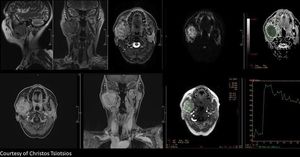

High resolution anatomical imaging (T2-w FSE in sagittal and coronal plane, T2-w IDEAL in axial plane and 3D LAVA-Flex in axial and coronal plane after Gd administration), DWI b800, ADC map and DCE PWI are shown here. Low ADC value and high perfusion (early wash-in and wash-out) should be noted. #MRI #mpMRI #radiology #head_neck #perfusion #diffusion #Gd #MRI_Technologist #MRITechnologist #MRI_Radiographer